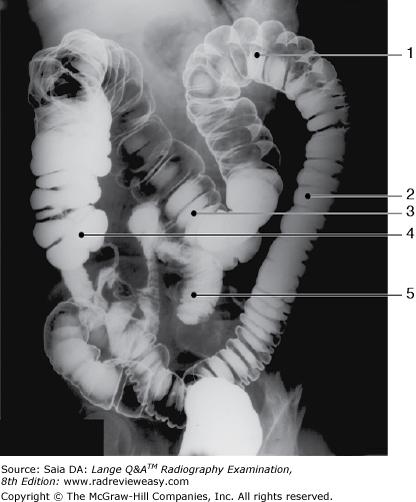

The structure indicated by the number 2 in Figure 6–11 is the

A ascending colon.

B descending colon.

C transverse colon.

D sigmoid colon.

-The figure shown is a double-contrast BE, oblique position. Since the left colic/splenic flexure (number 1) is “open,” this is either a RPO or LAO position. Also demonstrated are the descending colon (number 2), and transverse colon (number 3). Barium has refluxed into the ileum (number 5).

In which of the following positions was the radiograph in Figure A taken?

A RPO

B LPO

C AP axial

D Right lateral decubitus

-The pictured radiograph is an oblique position of the large bowel, illustrating an "open" view of the hepatic/right colic flexure and ascending colon, with the splenic/left colic flexure superimposed on the descending colon. Therefore, the radiograph must have been made in either an RAO (if the patient was prone) or an LPO (if the patient was supine) position. The LAO and RPO positions are used to demonstrate the splenic/left colic flexure and descending colon free of self-superimposition. AP or PA axial is generally used to visualize the rectosigmoid colon.